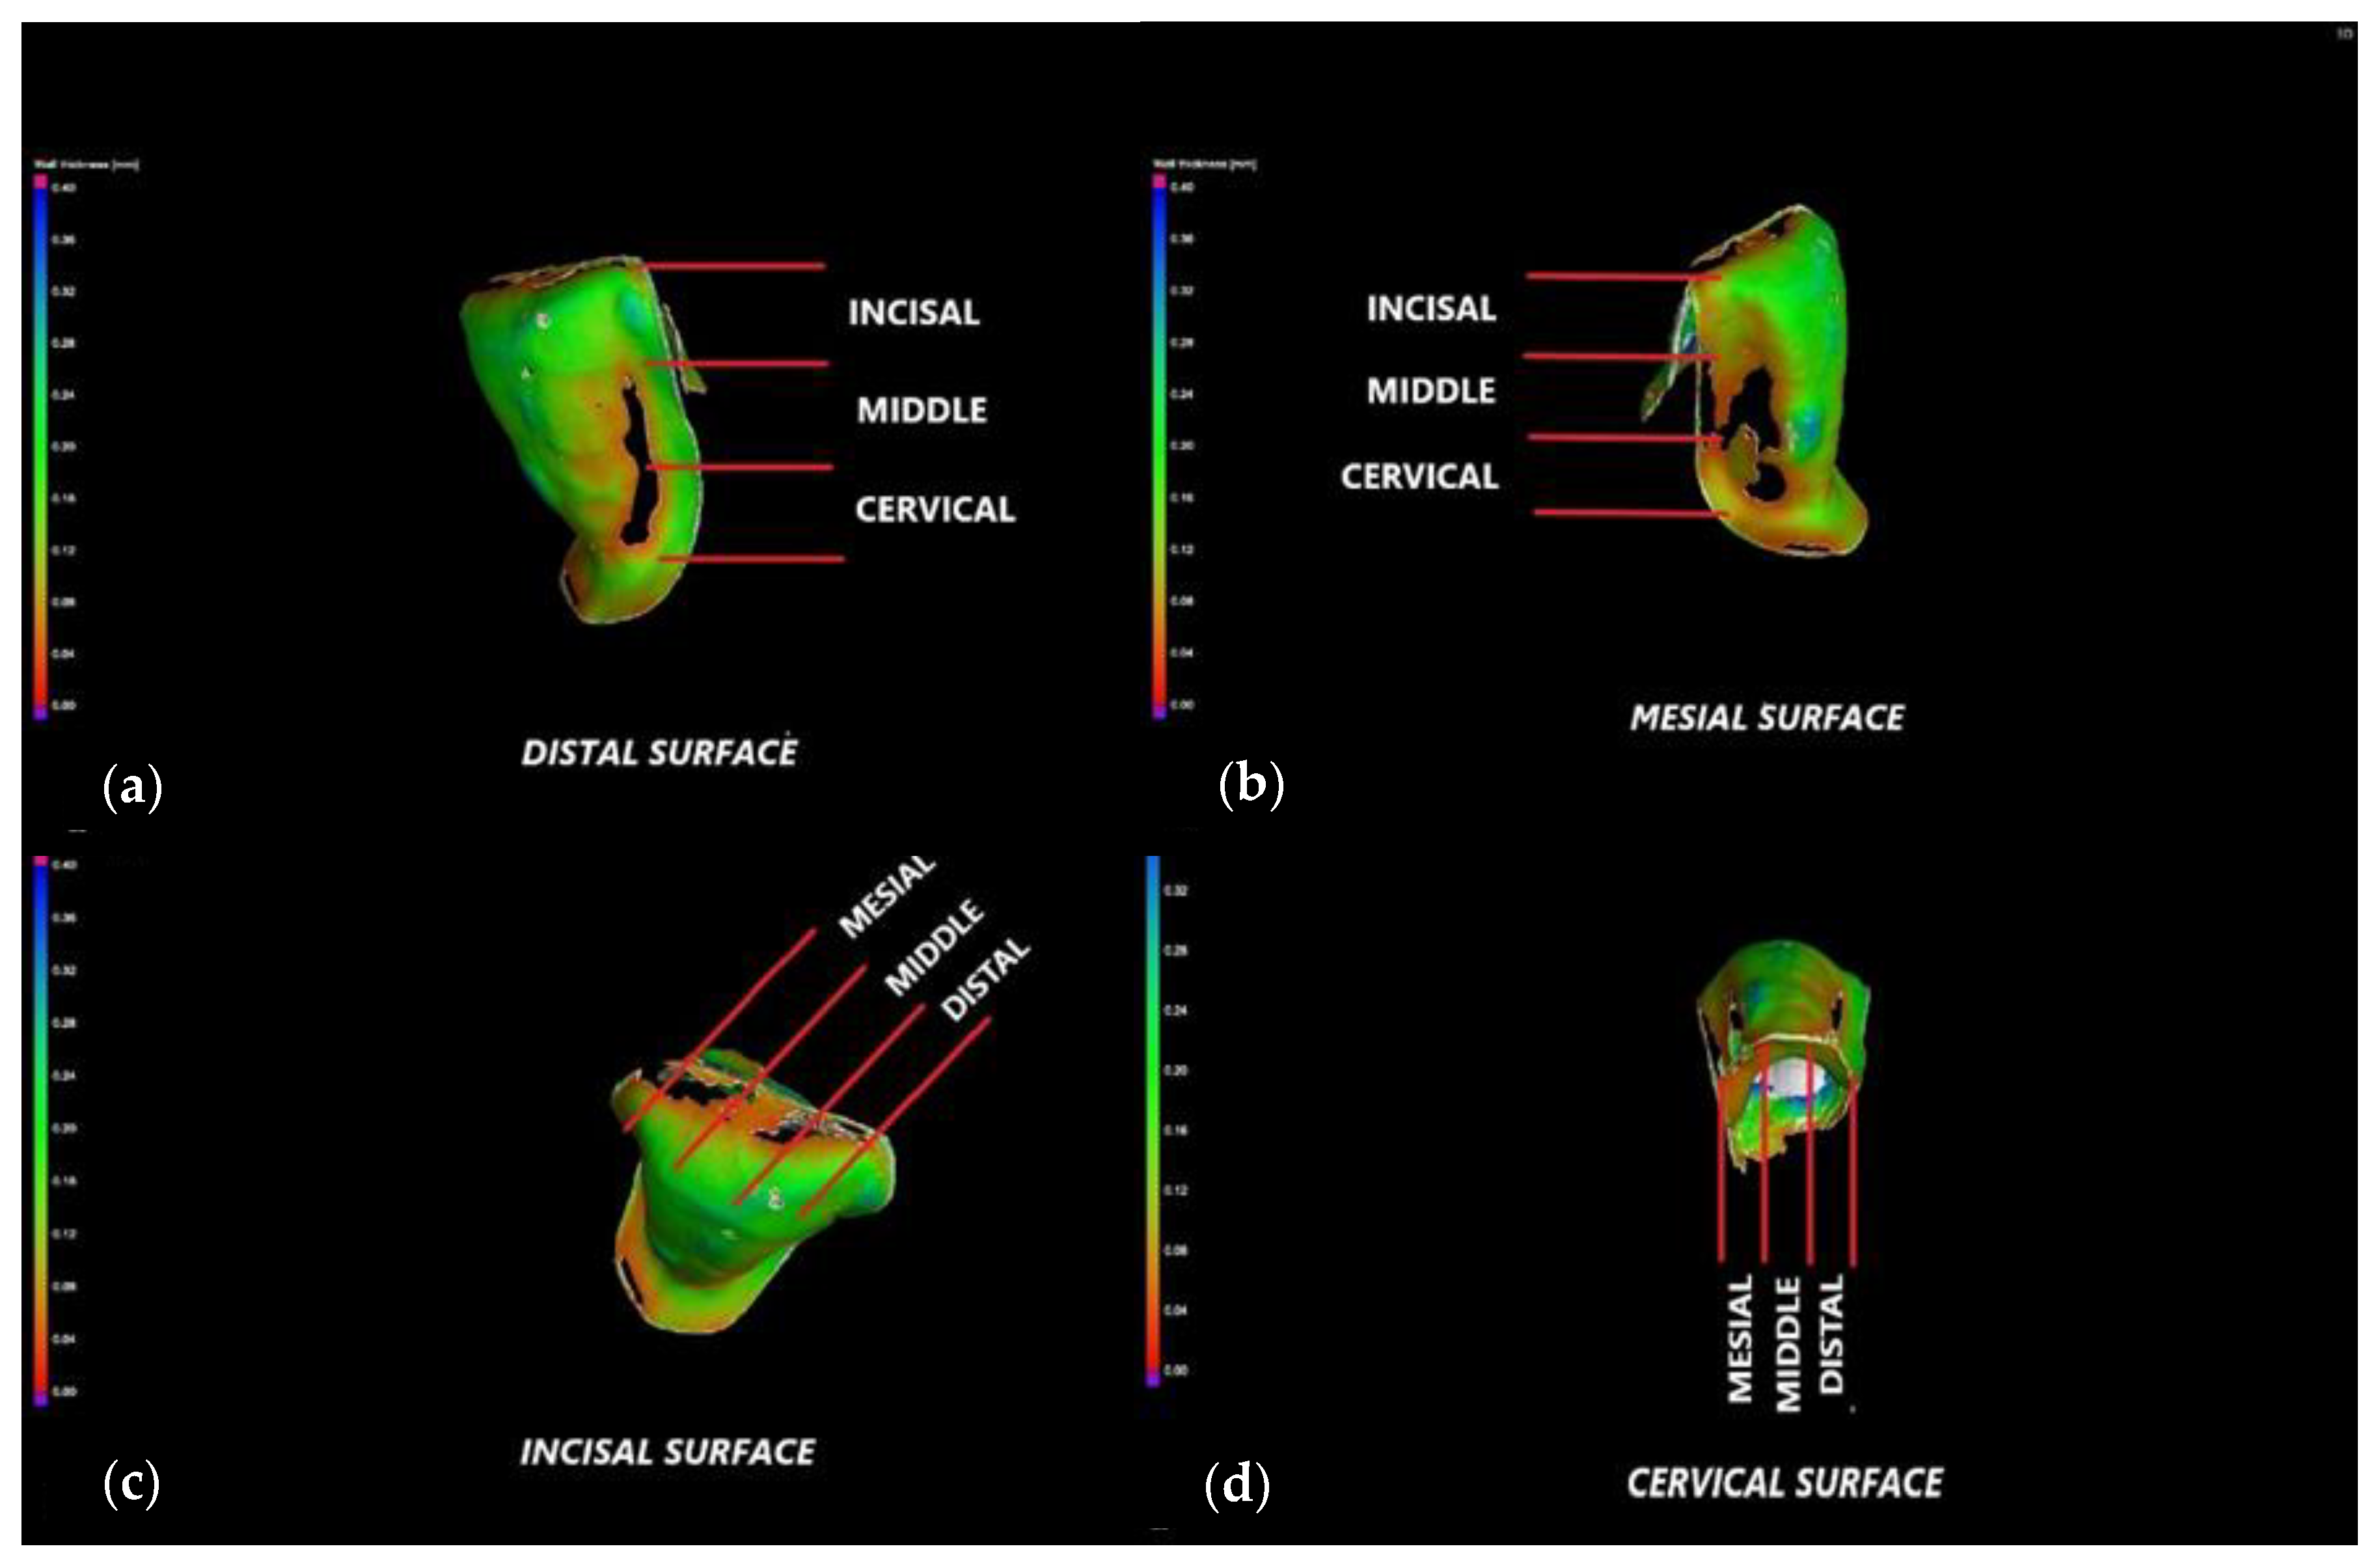

2.4. Micro-CT Investigations

3.2. Micro-CT

3.3. Mathematical Modeling of the Micro-CT Results

- The internal adaptation was considerably better for the CR group in comparison with CO, as the clinically accepted cement thickness/width of up to 120 μm covered 81.5% of the tooth surface for CR compared to 64.5% for CO. Such a thinner and more uniform layer of luting cement creates the premises for better protection of restorations from cement shrinkage, microleakage, tensile forces beneath the veneers and, eventually, debonding or fracture-aspects to be investigated in future work.

- Micro-CT proved to be reliable and precise to evaluate the internal adaptation of the restorations, as well as the porosities localized in the luting cement. It has the advantage of providing 3D information on the entire volume of dental cement (i.e., the interface between dental support and veneers). The more common and accessible tool, optical microscopy, provided valuable data regarding the marginal adaptation, with a good agreement with the micro-CT results, but cannot evaluate internal adaptation.